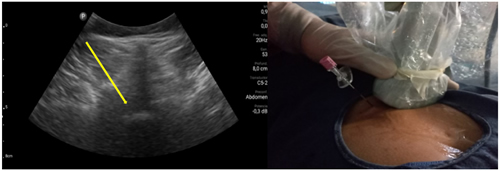

Pacientes y métodos: Un total de 25 pacientes con dolor radicular lumbosacro fueron seleccionados para recibir inyecciones epidurales interlaminares de esteroides en posición decúbito dorsal, utilizando la técnica ecoguiada en plano, en tiempo real, en eje corto o transversal. En todos los casos, un epidurograma de control fue realizado previo a la inyección de la solución de esteroides. El rendimiento de la técnica fue estudiado mediante la tasa de éxito de la misma, entendido como éxito a la obtención de un epidurograma sin necesidad de abandonar la técnica ecográfica en un tiempo menor a 10 minutos. El rendimiento del procedimiento fue estadísticamente evaluado por el método de la suma acumulativa (CUSUM), y la curva de aprendizaje aplicando este método fue construida.

Resultados: La distancia promedio desde la piel al complejo posterior evaluada por el escaneo ecográfico previo al procedimiento fue de 6,7 ± 1,8 cm. De los 25 procedimientos realizados, en 21 se alcanzó el espacio epidural sin ayuda de la fluoroscopia, en un tiempo promedio de 4,8 ± 1,2 minutos. Esto constituye una tasa de éxito del 84 %. En los cuatro procedimientos restantes el espacio epidural fue alcanzado con éxito mediante el uso complementario de la fluoroscopia.